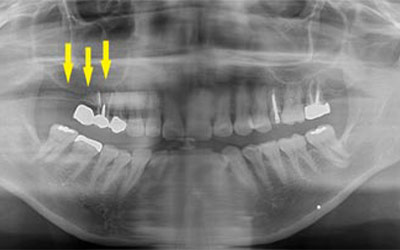

写真は初診時の患者様のレントゲン写真です。左右とも、上顎第一大臼歯を失っていました。通常のレントゲン写真では、骨量が十分かと思われましたが、CTを撮影してみると、黄色の矢印部位、左側では、少し骨の高さが足りませんでした。

-

CTを撮影して、測定すると、右側はギリギリ10mmぐらいの高さで、左側は6mmほどしかありませんでした。

そこで、左側はソケットリフトを併用して行いました。インプラント埋入手術後のCT、黄色の矢印部分、インプラント周囲にドーム状に補填材が白く写り、インプラントがしっかりと埋入できています。